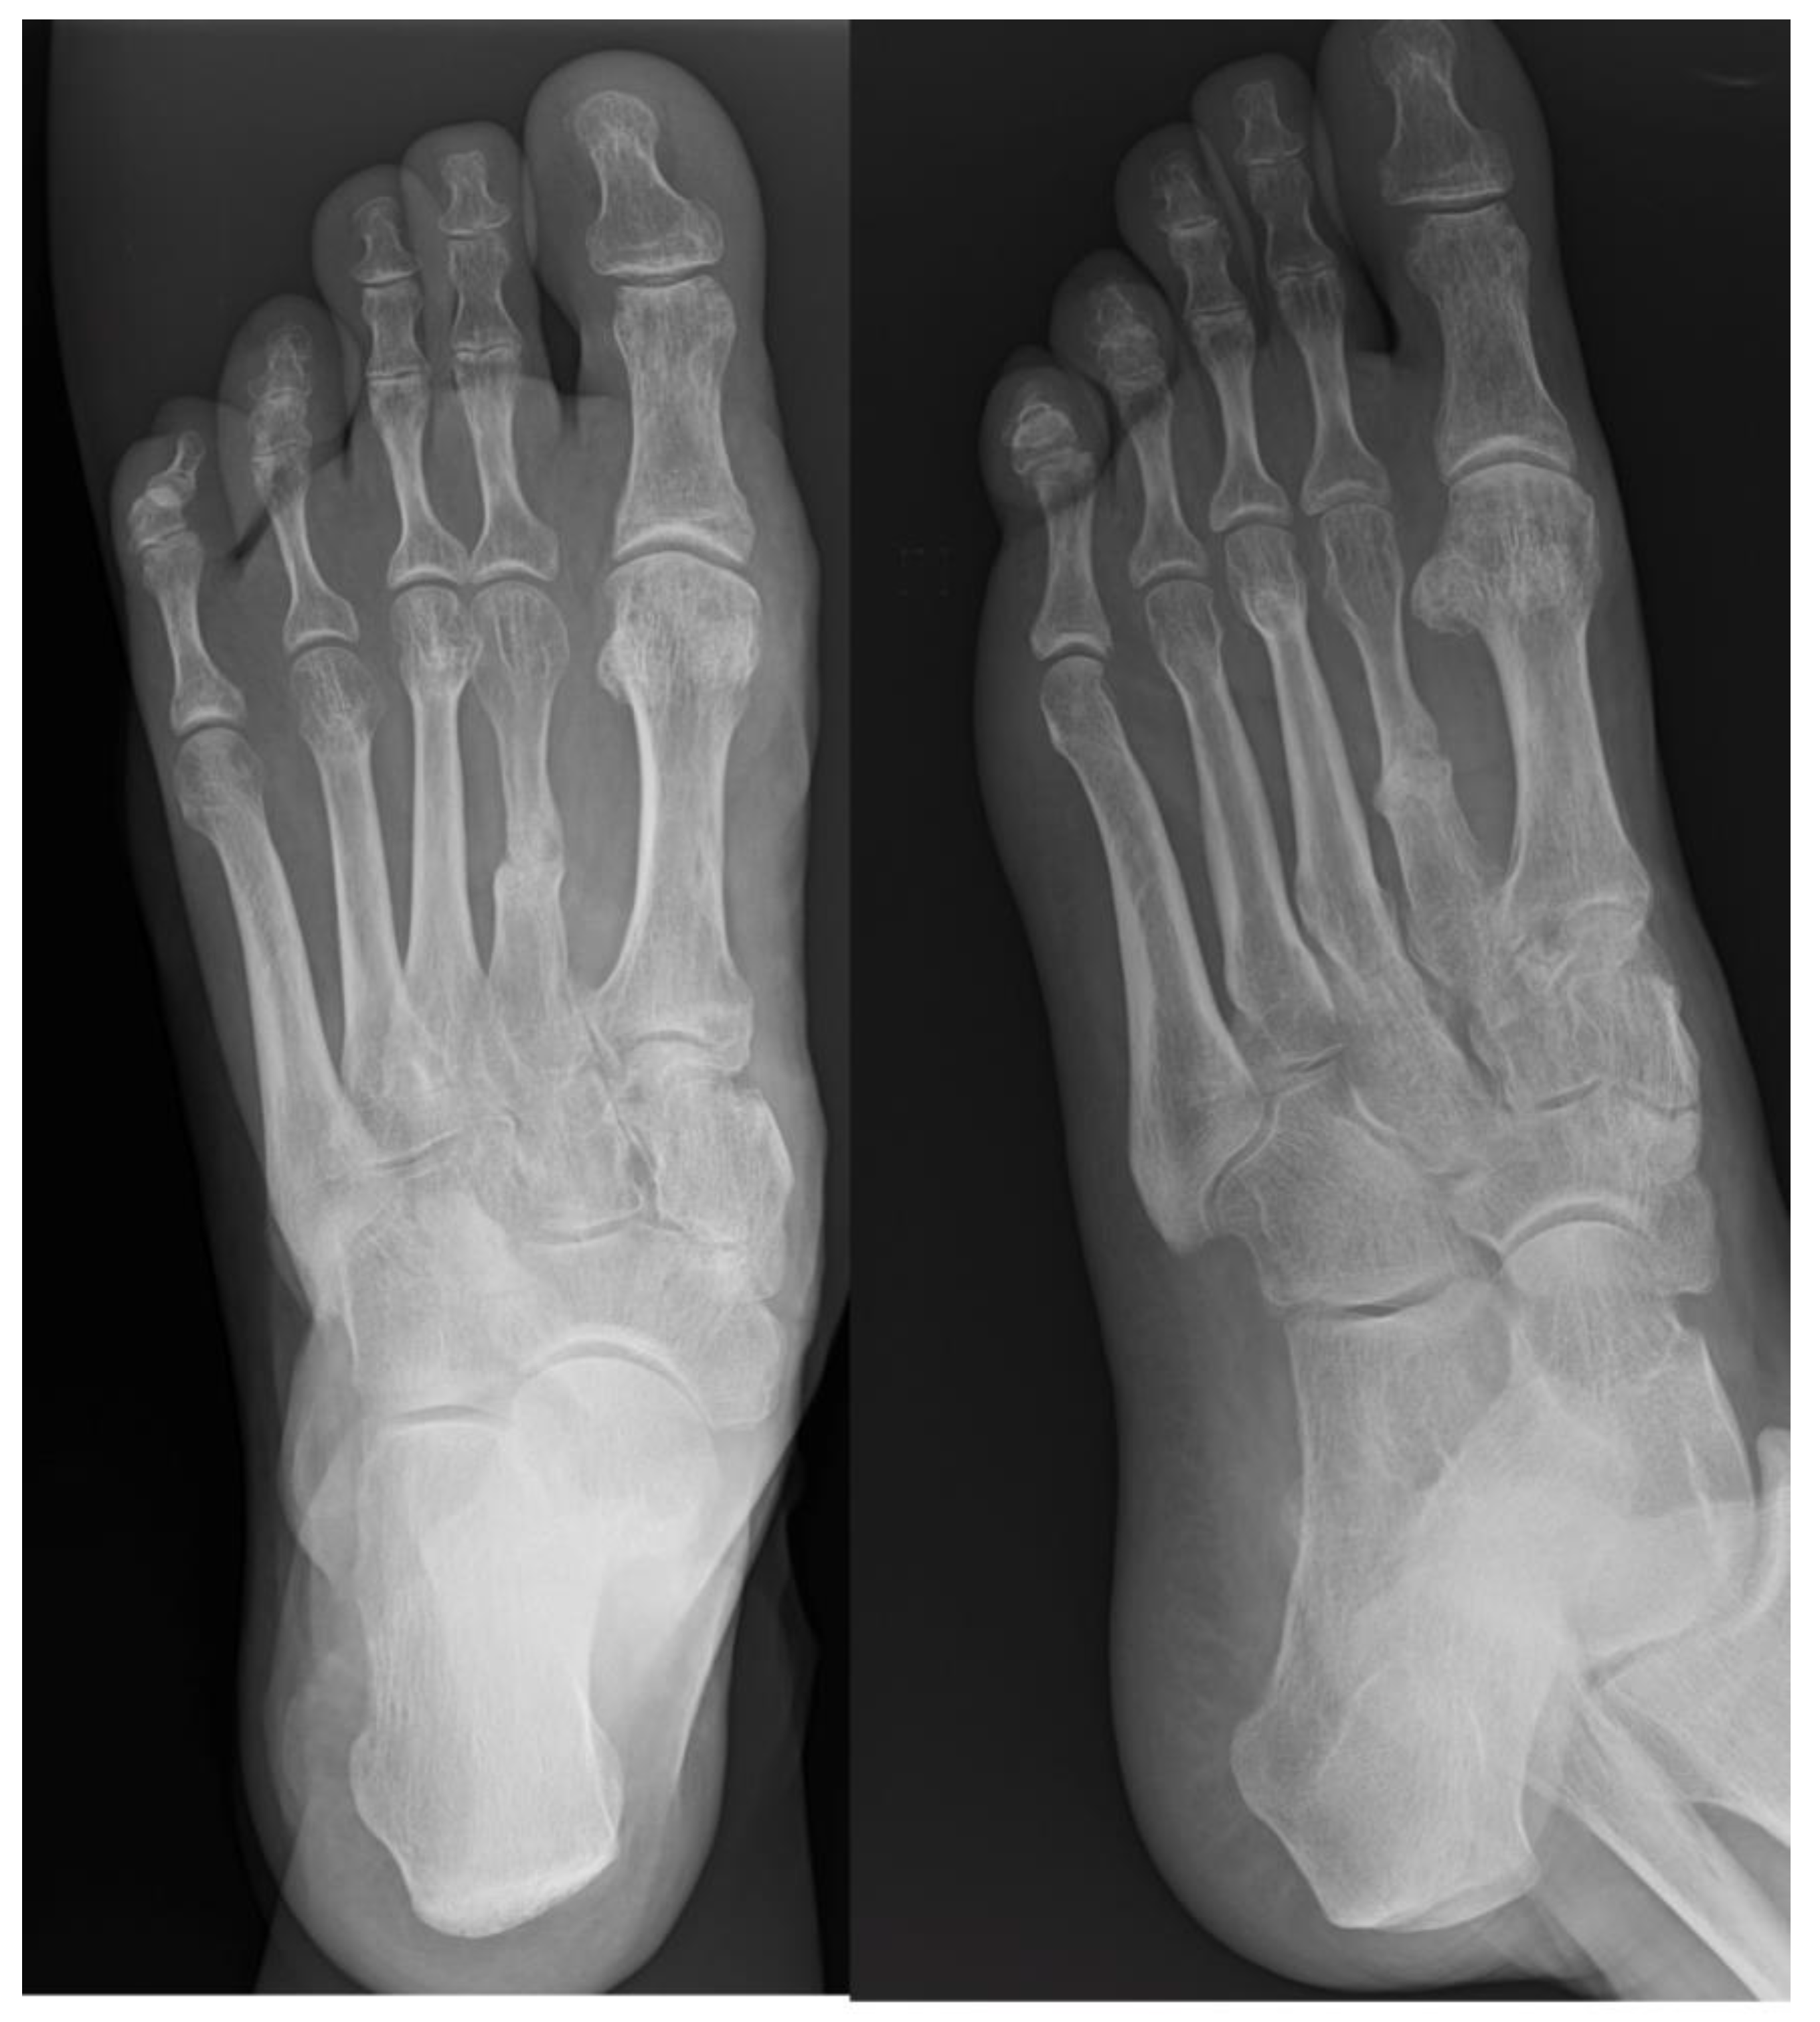

Subsequently, through a distal dorsal approach, a retrocapitatum oblique cylindrical osteotomy was performed to shorten the third and fourth metatarsals for realignment of the metatarsal formula. Autologous bone cylinders harvested from the third and fourth metatarsals were used as autografts at the pseudoarthrosis site (Figure 2). It is crucial to execute all osteotomies with consistent obliquity to facilitate optimal alignment of the bony surfaces.

Figure 2. The two bone cylinders harvested from the third and fourth metatarsals used as autografts at the pseudoarthrosis site.